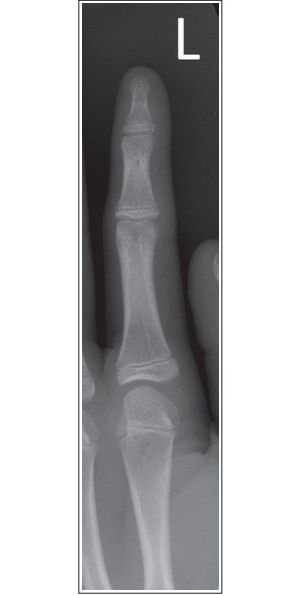

What’s wrong with this oblique finger projection?

More than 45 degrees obliquity

Over-rotation

What’s wrong with this oblique finger?

Less than 45 degrees obliquity

Under-rotation